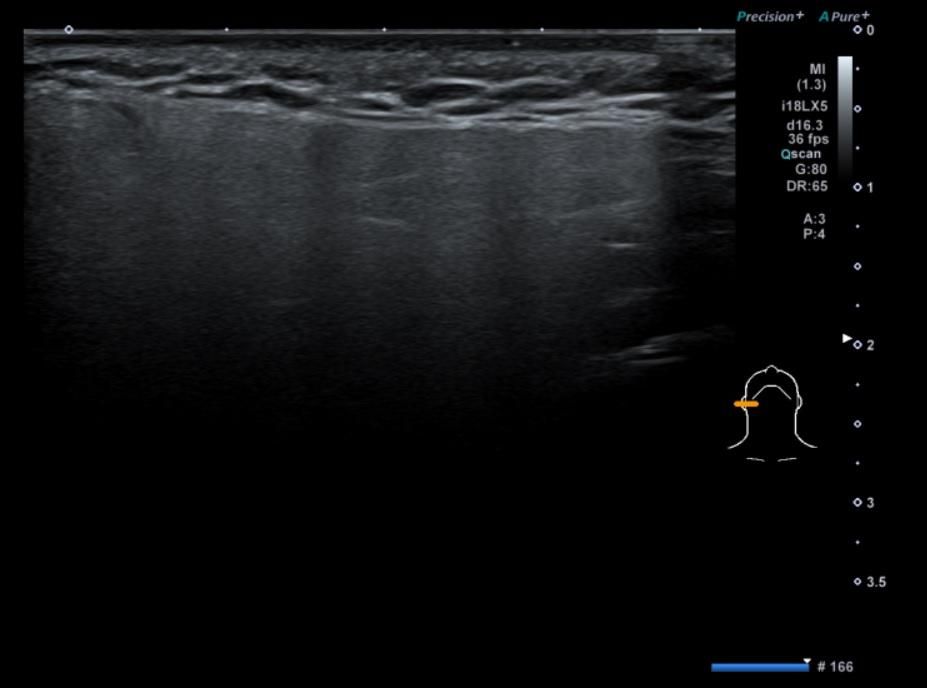

• 2번 째 사진